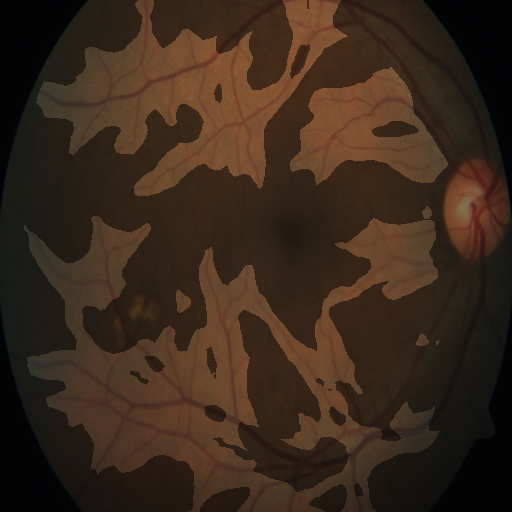

The diabetic retinopathy classification [38] (APTOS), is a medical imaging dataset containing retina images taken using fundus photography. The images are classified in one of five classes, depending on the severity of their diabetic retinopathy. Examples of said classes are shown in Figure 8. Domain experts diagnose the diabetic retinopathy severity based on visual cues such as micro-aneurysms, hard exudates, hemorrhages and abnormal blood vessel growth. During the development of these models, extracting concepts allows for a better explanation, of which visual cues are used by models, and how important they are in their prediction process.

After the execution of ECLAD, three concepts with importance scores above 0.6 were extracted. In addition, these concepts were aligned with the visual cues used by domain experts, as seen in Figure 8.

The concepts and , with importance scores of 1.0 and 0.8 respectively, relate to micro-aneuryms and hard-exudates. As secondary visual cues, the concepts and with importance scores of 0.7 and 0.57, relate to different formations of blood vessels. As a tangential insight, none of the concepts were specifically related to large hemorrhages. Paradoxically, the analyzed model does use a minimal set of visual cues important to human experts. Yet, not all cues that human experts would consider relevant are being used by the CNN in the prediction process.